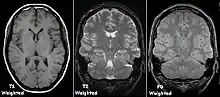

| Spin echo | T1 weighted | T1 | Measuring spin–lattice relaxation by using a short repetition time (TR) and echo time (TE). |

Standard foundation and comparison for other sequences |

| T2 weighted | T2 | Measuring spin–spin relaxation by using long TR and TE times |

| Proton density weighted | PD | Long TR (to reduce T1) and short TE (to minimize T2).[7] | Joint disease and injury.[8]

Each tissue returns to its equilibrium state after excitation by the independent relaxation processes of T1 (spin-lattice; that is, magnetization in the same direction as the static magnetic field) and T2 (spin-spin; transverse to the static magnetic field). To create a T1-weighted image, magnetization is allowed to recover before measuring the MR signal by changing the repetition time (TR). This image weighting is useful for assessing the cerebral cortex, identifying fatty tissue, characterizing focal liver lesions, and in general, obtaining morphological information, as well as for post-contrast imaging. To create a T2-weighted image, magnetization is allowed to decay before measuring the MR signal by changing the echo time (TE). This image weighting is useful for detecting edema and inflammation, revealing white matter lesions, and assessing zonal anatomy in the prostate and uterus.